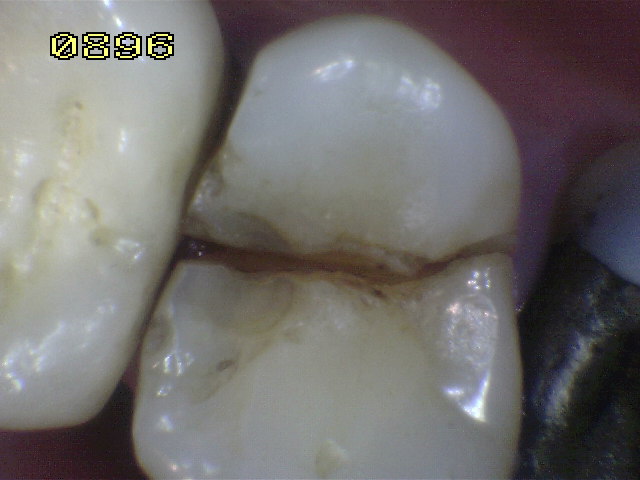

Dos conductos bien delimitados, ensanchados con limas rotatorias, recidiva de caries en distal. |